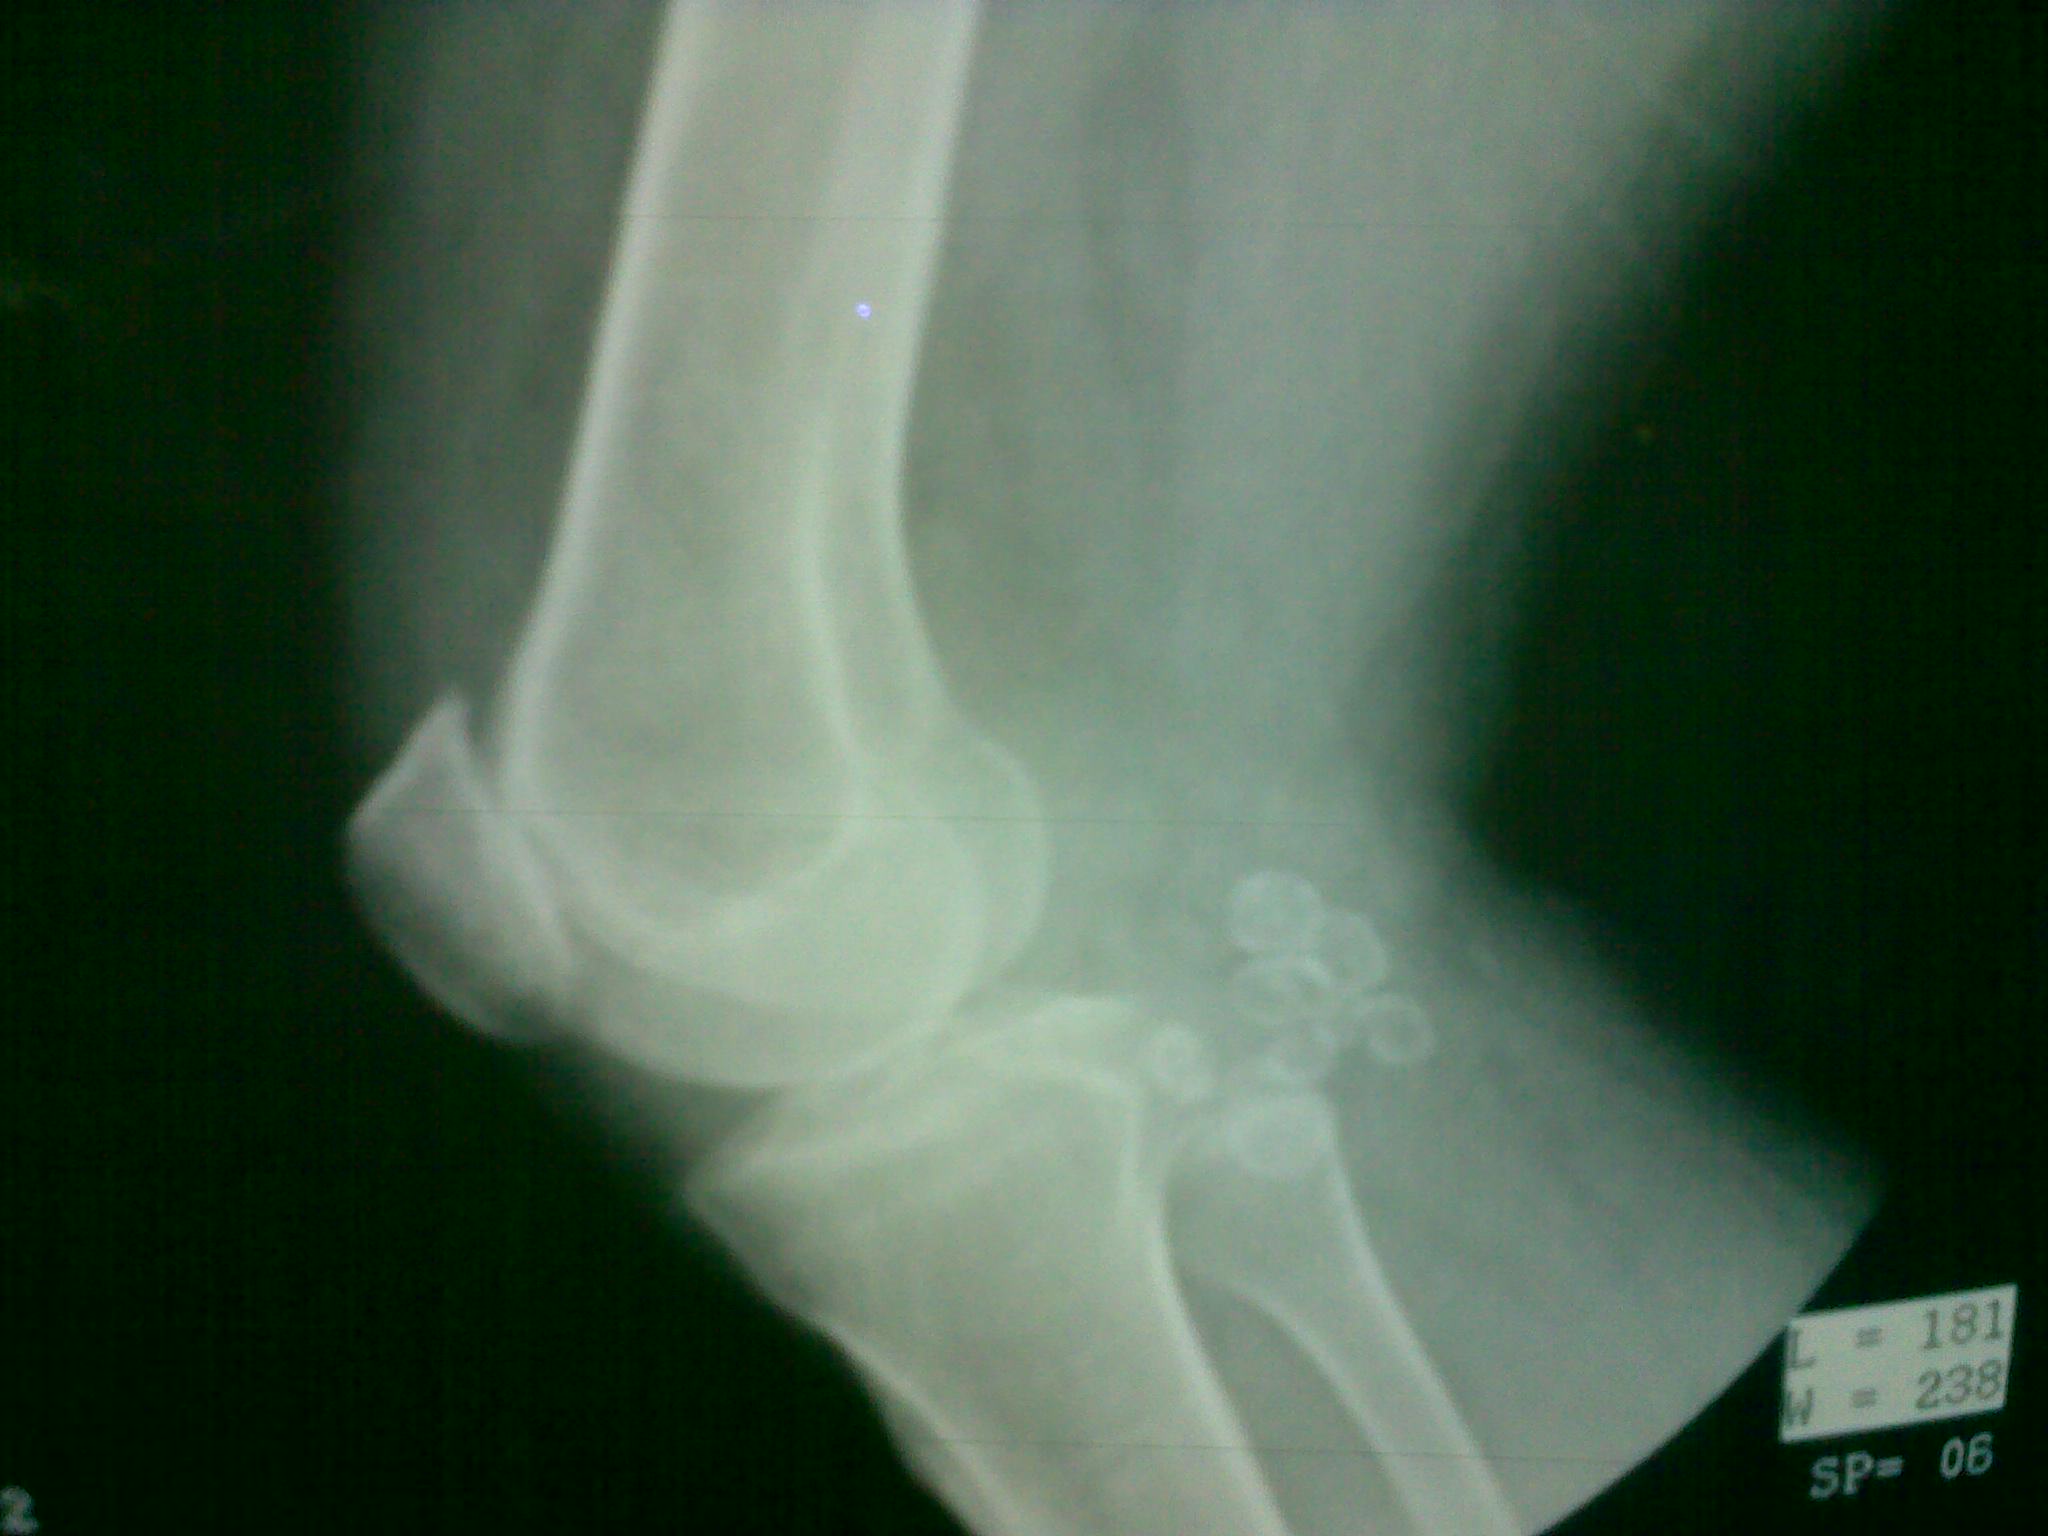

Photo courtesy of AKha